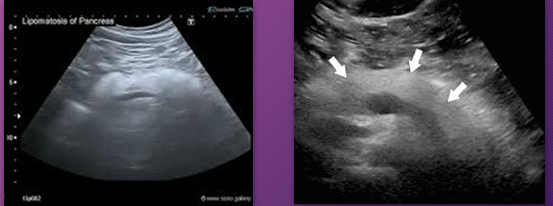

Pancreatic _______ is fat that replaces or infiltrates the pancreas

lipomatosis

Pancreatic lipomatosis is _____ that _____ or _____ the pancreas

fat; replaces; infiltrates